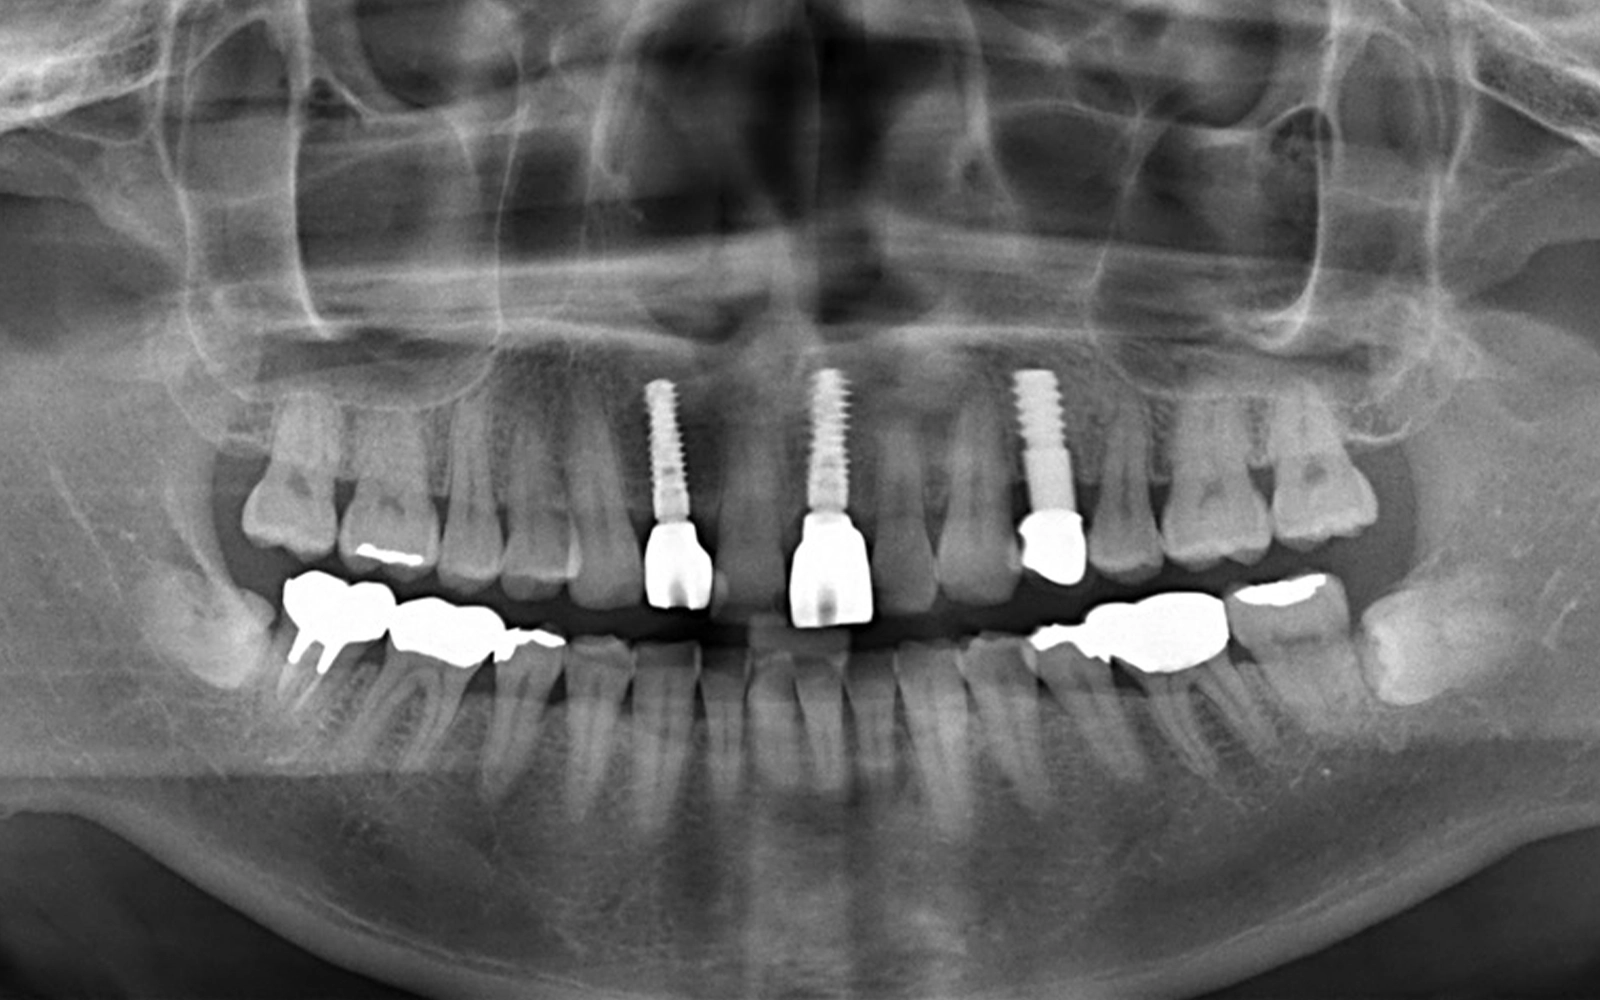

レントゲン写真では、当院で治療した「2本のインプラント体」が骨の中にしっかりと埋入されていることが確認できます。(*治療前のレントゲン写真を見るとわかる通り、当院で治療する前から1本インプラントが入っていたので、治療後は合計3本のインプラントが埋め込まれていることになります。)

そして、インプラント(写真内に写っている白いネジ状の物体)の周囲に骨が十分に存在しており、骨吸収(骨が溶けて減ること)は認められません。

抜歯と同時に埋入を行ったにもかかわらず、周囲の骨がしっかりと保たれていることは、抜歯即時埋入の大きな利点です。